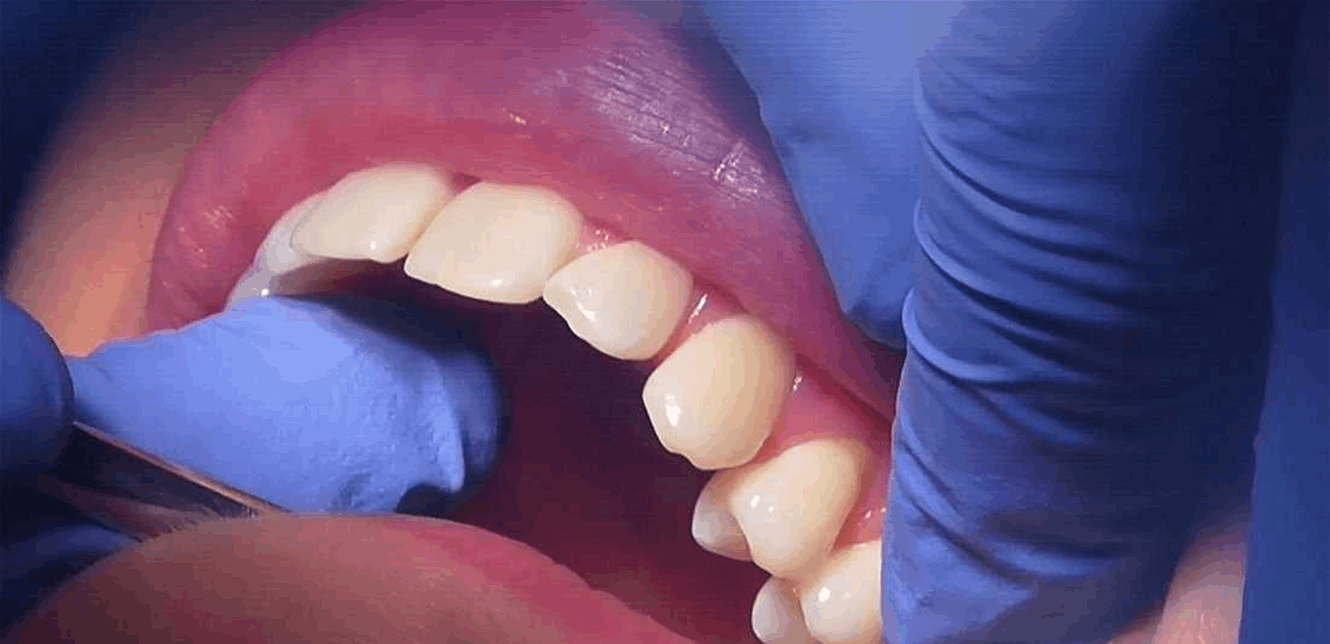

وأوضح أنه يوضع مباشرة على الأسنان دون أي تدخل جراحي، متوقعاً إطلاقه في الأسواق العام المقبل.

يعمل الهلام من خلال محاكاة طريقة عمل البروتينات الطبيعية التي توجه نمو المينا خلال مرحلة الطفولة. عند وضعه على الأسنان، يشكل طبقة قوية تملأ الثقوب والتشققات، ثم يمتص الأيونات والكالسيوم والفوسفات من اللعاب لتعزيز نمو المعادن بانتظام، مما يؤدي في النهاية إلى استعادة بنية وخصائص المينا الصحية.

وأكد الدكتور أبشر حسن، المؤلف الرئيسي للدراسة، أن التجارب الميكانيكية كشفت أن المينا المتجددة تعمل تماماً مثل المينا الطبيعية. ويأمل الفريق من خلال شركتهم الناشئة “مينتيك بايو” طرح أول منتجين العام المقبل، مما قد يشكل طوق نجاة للملايين الذين يعانون من مشاكل تسوس الأسنان حول العالم. (سكاي نيوز)